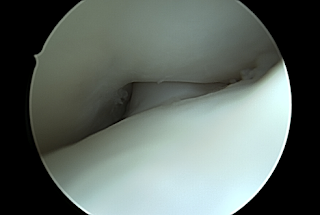

Jacco ging met zijn camera naar de intercondylaire ruimte, waar de voorste kruisband zich mooi liet zien. Die zag er godzijdank goed uit: intact. Net als de achterste kruisband. Wat wel meteen opviel was het gebrek aan ruimte in de femorale notch. “Precies wat ik had verwacht”, zei Jacco. Hij vervolgde: “Dit is wel een heel klein ‘notchje'”, met verkleinwoord. Dat past niet goed. Hij liet me zien wat er gebeurde als mijn been richting strekking ging. Met de camera in mijn knie bewoog hij mijn knie van flexie naar extensie. Die kruisband van 9 mm loopt hartstikke vast. Onmogelijk om strekking te bereiken. Ik was opgelucht om de oorzaak te zien. Mijn gevoel dat er iets niet klopte, dat ik al heel snel na de voorste kruisbandreconstructie had, heeft altijd goed gezeten en werd nu bevestigd.

Notch impingement na eerdere voorste kruisbandoperatie

Notch impingement: de notch is veel te smal voor de kruisband

Volledige extensie is daardoor onmogelijk